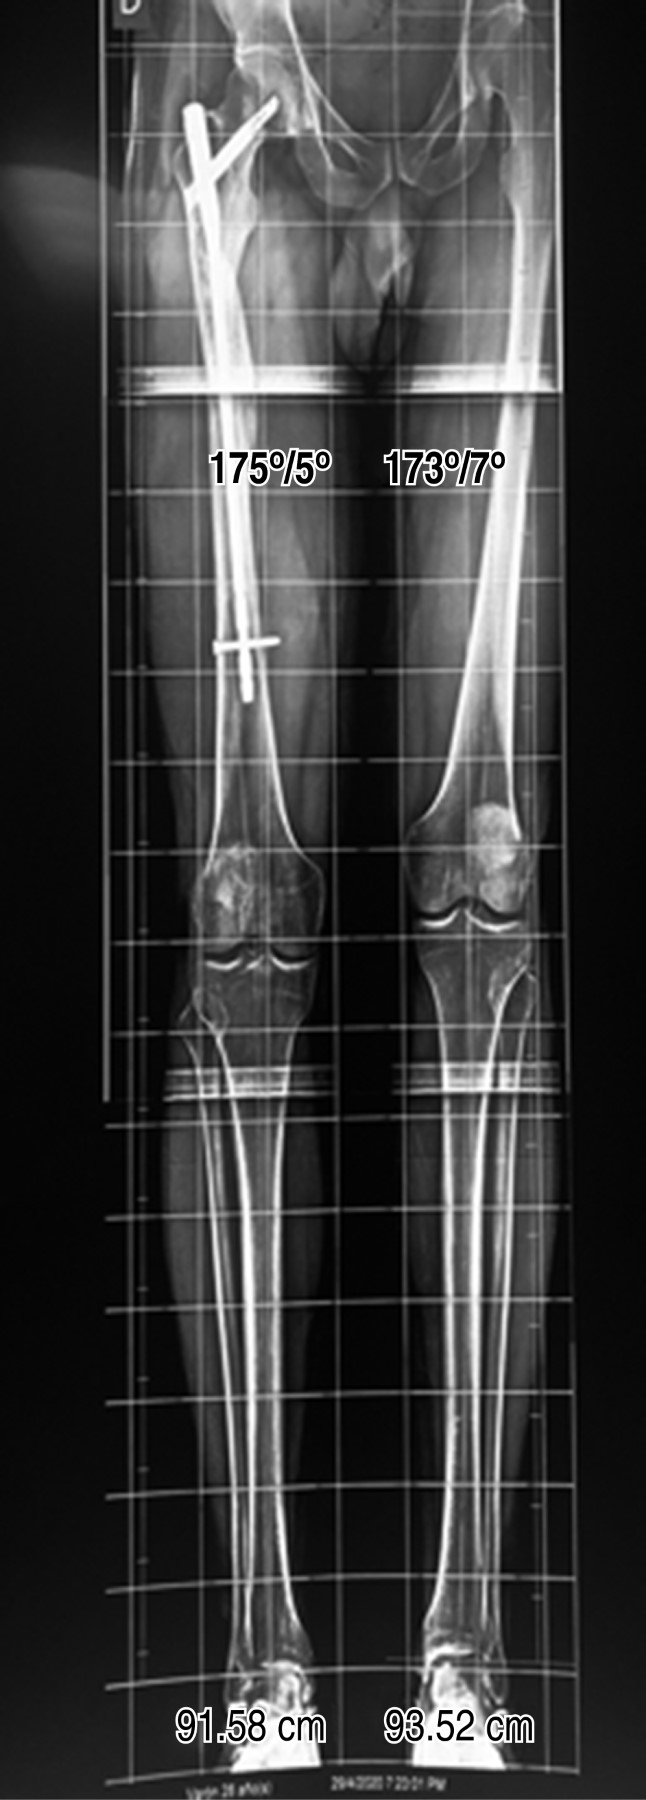

Las radiografías de cadera derecha en proyección anteroposterior (Figura 1) y lateral (Figura 2), así como radiografías de eje mecánico (Figura 3), evidenciando fractura consolidada de fémur diafisario derecho, acortamiento de 2.04 cm de miembro pélvico derecho a expensas de fémur y clavo centromedular anterógrado de entrada trocantérica. La radiografía lateral de cadera derecha revela protrusión posterior de la hélice del clavo centromedular a través de la cabeza femoral encontrándose en contacto con pared acetabular posterior. Este contacto condiciona erosión de pared acetabular alrededor de la protrusión.

Figura 3